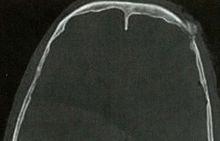

頂結節A

左側額、頂骨骨折;顱內積氣;頭皮血腫

注A、B:頭部CT軸位片。

【影像徵象】左側額、頂骨骨皮質斷裂,左側頂骨內板向內凹陷,顱內見點狀氣體影。

【影像擬診】左側額、頂骨骨折;顱內積氣;頭皮血腫。

【最終診斷】左側額、頂骨骨折;顱內積氣;頭皮血腫。

【述評】腦顱骨骨折以頂骨骨折多見,可以是開放型和閉合型。本例為開放型,顱內如果見到氣體即提示為開放型,有時顱內進氣很少,閱片是應仔細觀察。顱骨骨折可以是線樣、凹陷性、粉碎性和顱縫分離等類型。顱骨骨折通常在遭受到直接暴力下發生,由於頭皮軟組織的特點,局部通常會形成頭皮血腫,所以閱片時應重點在有頭皮血腫的位置仔細觀察是否有骨折,特別是細小的骨折,減少遺漏病變。線性骨折應要注意同顱縫相區別,線性骨折一般清晰、銳利,骨縫一般不那么銳利,雙側對稱。如果顱縫寬度成人>1.5mm、兒童>2mm或雙側相差>1mm,應視為顱縫分離。顱骨骨折時,顱內有時可見到顱內板下的血腫,本例就可見硬膜外血腫或硬膜下血腫(未展示),一般情況在骨折局部硬膜外血腫居多,對沖部位硬膜下血腫居多。發生於顱底的骨折,有時需薄層掃描方可顯示,需要仔細觀察,因為臨床意義重大。